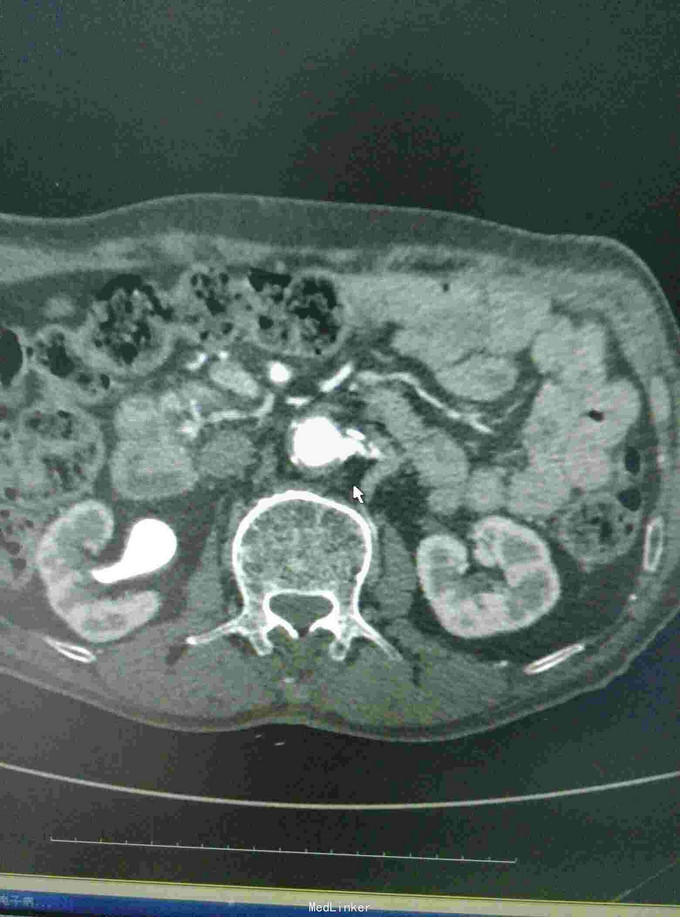

男患,74岁,间歇性跛行2年伴右足疼痛9+月,2年前无明显诱因出现间歇性跛行,行走后伴下肢远端疼痛、乏力,休息后缓解,无红肿发热及感觉异常,后行走距离渐变短,9月前加重伴远端静息痛。

左下肢皮温降低,左足背可见紫红色淤斑,左股动脉扪及微弱波动。下肢血管成像提示:双下肢动脉节段性不同程度狭窄、闭塞。

双下肢动脉硬化闭塞症 手术:左侧髂动脉探查术,术中探查股动脉,导丝导管尝试通过闭塞段髂动脉,但反复尝试无法继续。右侧也无法通过。家属放弃。